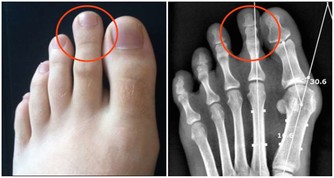

我們現在相反了,所以很多病都來了,肥胖也來了,糖尿病也來了,痛風也來了。